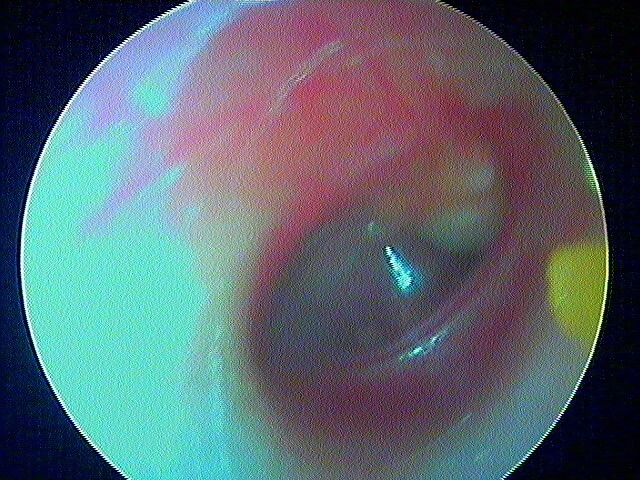

3/2 barotraumatique

– stade I : hyperhémie du manche du marteau et de la pars flaccida ;

– stade II : tympan rétracté, congestif, immobile

– stade III : aspect d'otite séromuqueuse

– stade IV : aspect otite séro-hémorragique, otohématome

– stade V : perforation

Ici des stades V perforés